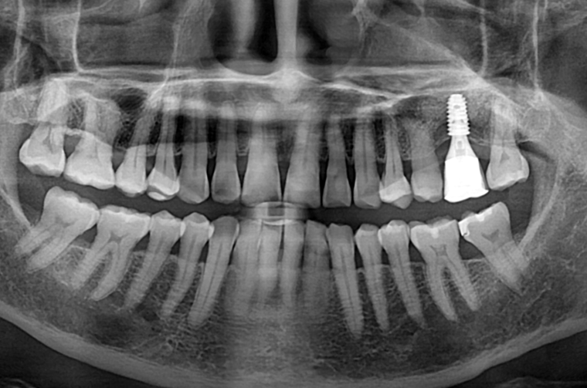

상악동 측방 거상술.

After

위 케이스는 이미 상악의 잇몸 뼈가 많이 부족하여

상악동 거상술을 시행하여 뼈이식을 충분히 시행한 후

임플란트 식립을 통해 보철을 완료하였습니다.